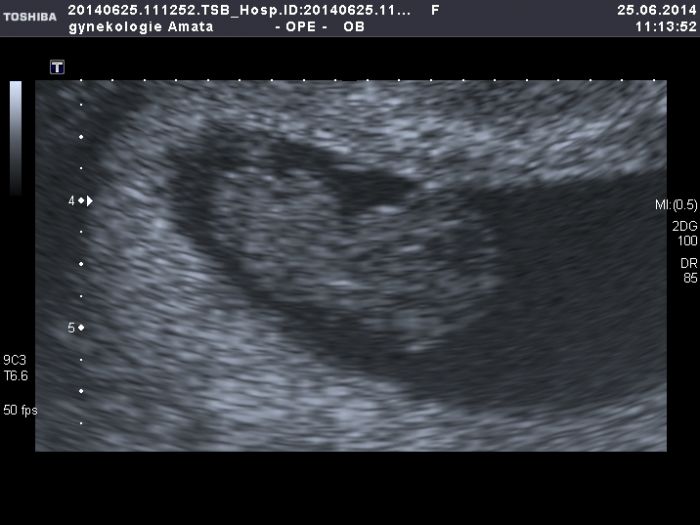

Ahoj maminky:-)tak mam dnesni kontrolu zasebou.vse je v poradku,podle utz jsem dnes 8+5tt,takze o tri tydny mladsi.mame 21mm.Kristynka byla semnou,koukala se na miminko.vsechno jsem ji vysvetlila a ted furt chodi a rika,ze mame v brisku miminko :-D tak take konecne prikladam svou prvni fotecku ;-)mejte krasny den